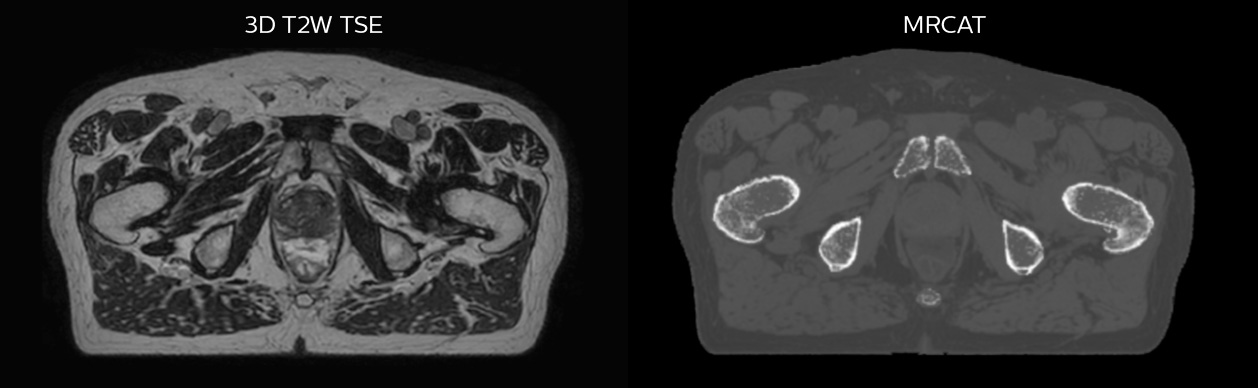

Prostate MR-only radiotherapy planning with use of rectal spacer

Hôpital de La Tour uses an implanted rectal spacer (SpaceOAR®, Boston Scientific) for patients receiving prostate radiotherapy to provide space between the rectum and prostate. 3D T2W TSE MRI provides excellent rectal spacer visualization and is used for OAR and target contouring. The dose plan is calculated on the MRCAT dataset.

Simulation imaging

Tranversal 3D T2W TSE with Compressed SENSE, acquired on Ingenia MR-RT 1.5T (left).

On-console generated MRCAT (right).